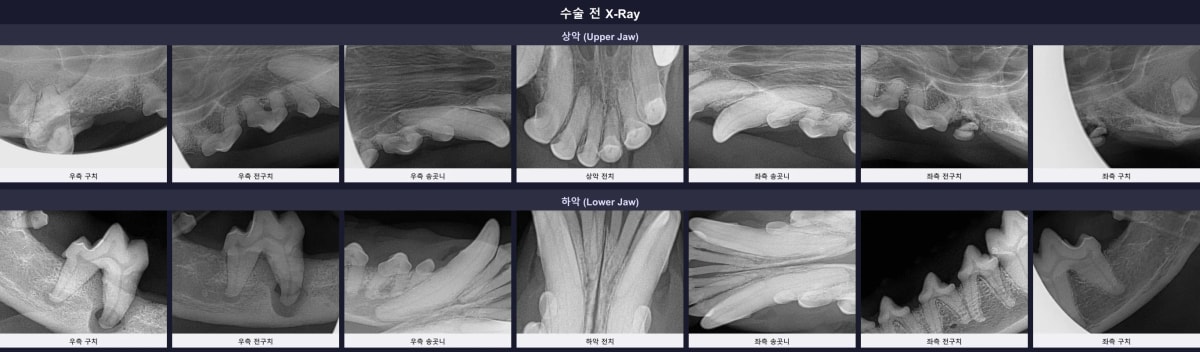

3. 수술 전 구강 방사선(X-ray) 검사 소견

마취 후 촬영한 구강 방사선 사진에서 하루의 심각한 구강 상태가 여실히 드러났습니다. 문제의 우측 하악 어금니(409번)는 치조골 흡수(잇몸뼈가 녹는 현상)가 뿌리 끝까지 진행되어 치아가 허공에 떠 있는 듯한 위태로운 상태였습니다. 이외에도 다수의 앞니와 어금니에서 심한 치조골 소실(ABL3 단계)이 관찰되었습니다.

수술 전 하루의 구강 방사선 사진, 심각한 치조골 흡수 및 잔존치근 소견